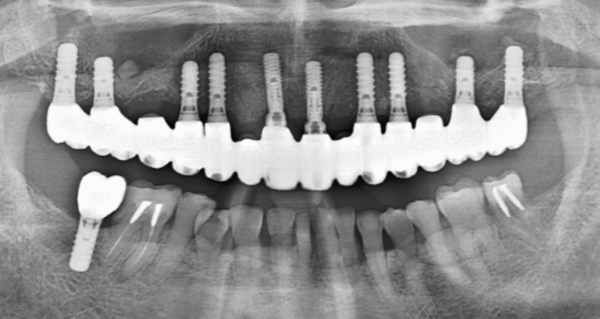

嚙む力がかなり強く、入れ歯(総義歯)が度々壊れるため、インプラント治療をすることに。

インプラント本数 11本 (ストローマンインプラント)(ジルコニアセラミック)(10年保証)